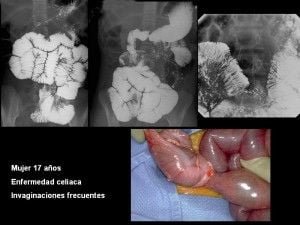

Abdomen, aparato digestivo y via biliarTécnicas de Exploración Radiológica Tránsito del intestino delgado Parte II 28 junio, 2012 Tidito Transito intestinal contraste simple Transito intestinal doble contraste yeyuno e ileon Patologia de Transito intestinal – Enfermedad celiaca Tumor maligno ileon terminalEnfermedad inflamatoria intestinal